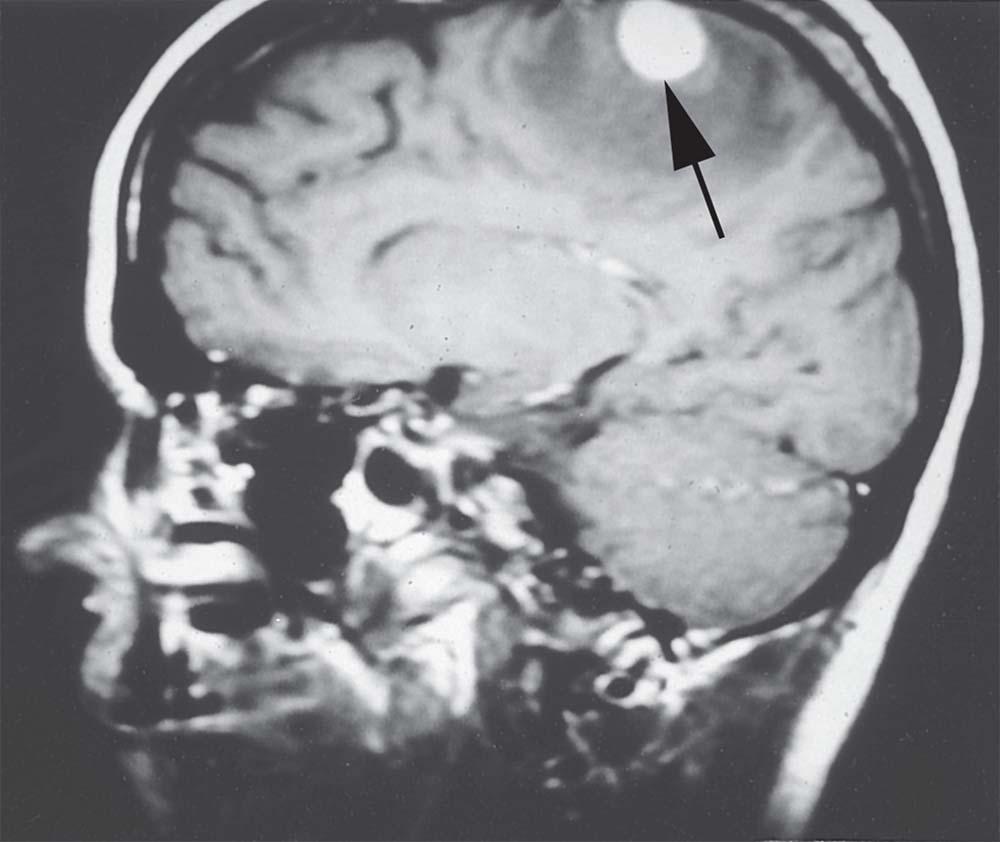

The nurse is caring for a patient with a history of lung cancer. After presenting to the clinic with headaches, the provider obtains this image. Which type of tumor is most likely the cause?

1.Primary

2.Gliomas

3.Oligodendrogliomas

4.Metastatic